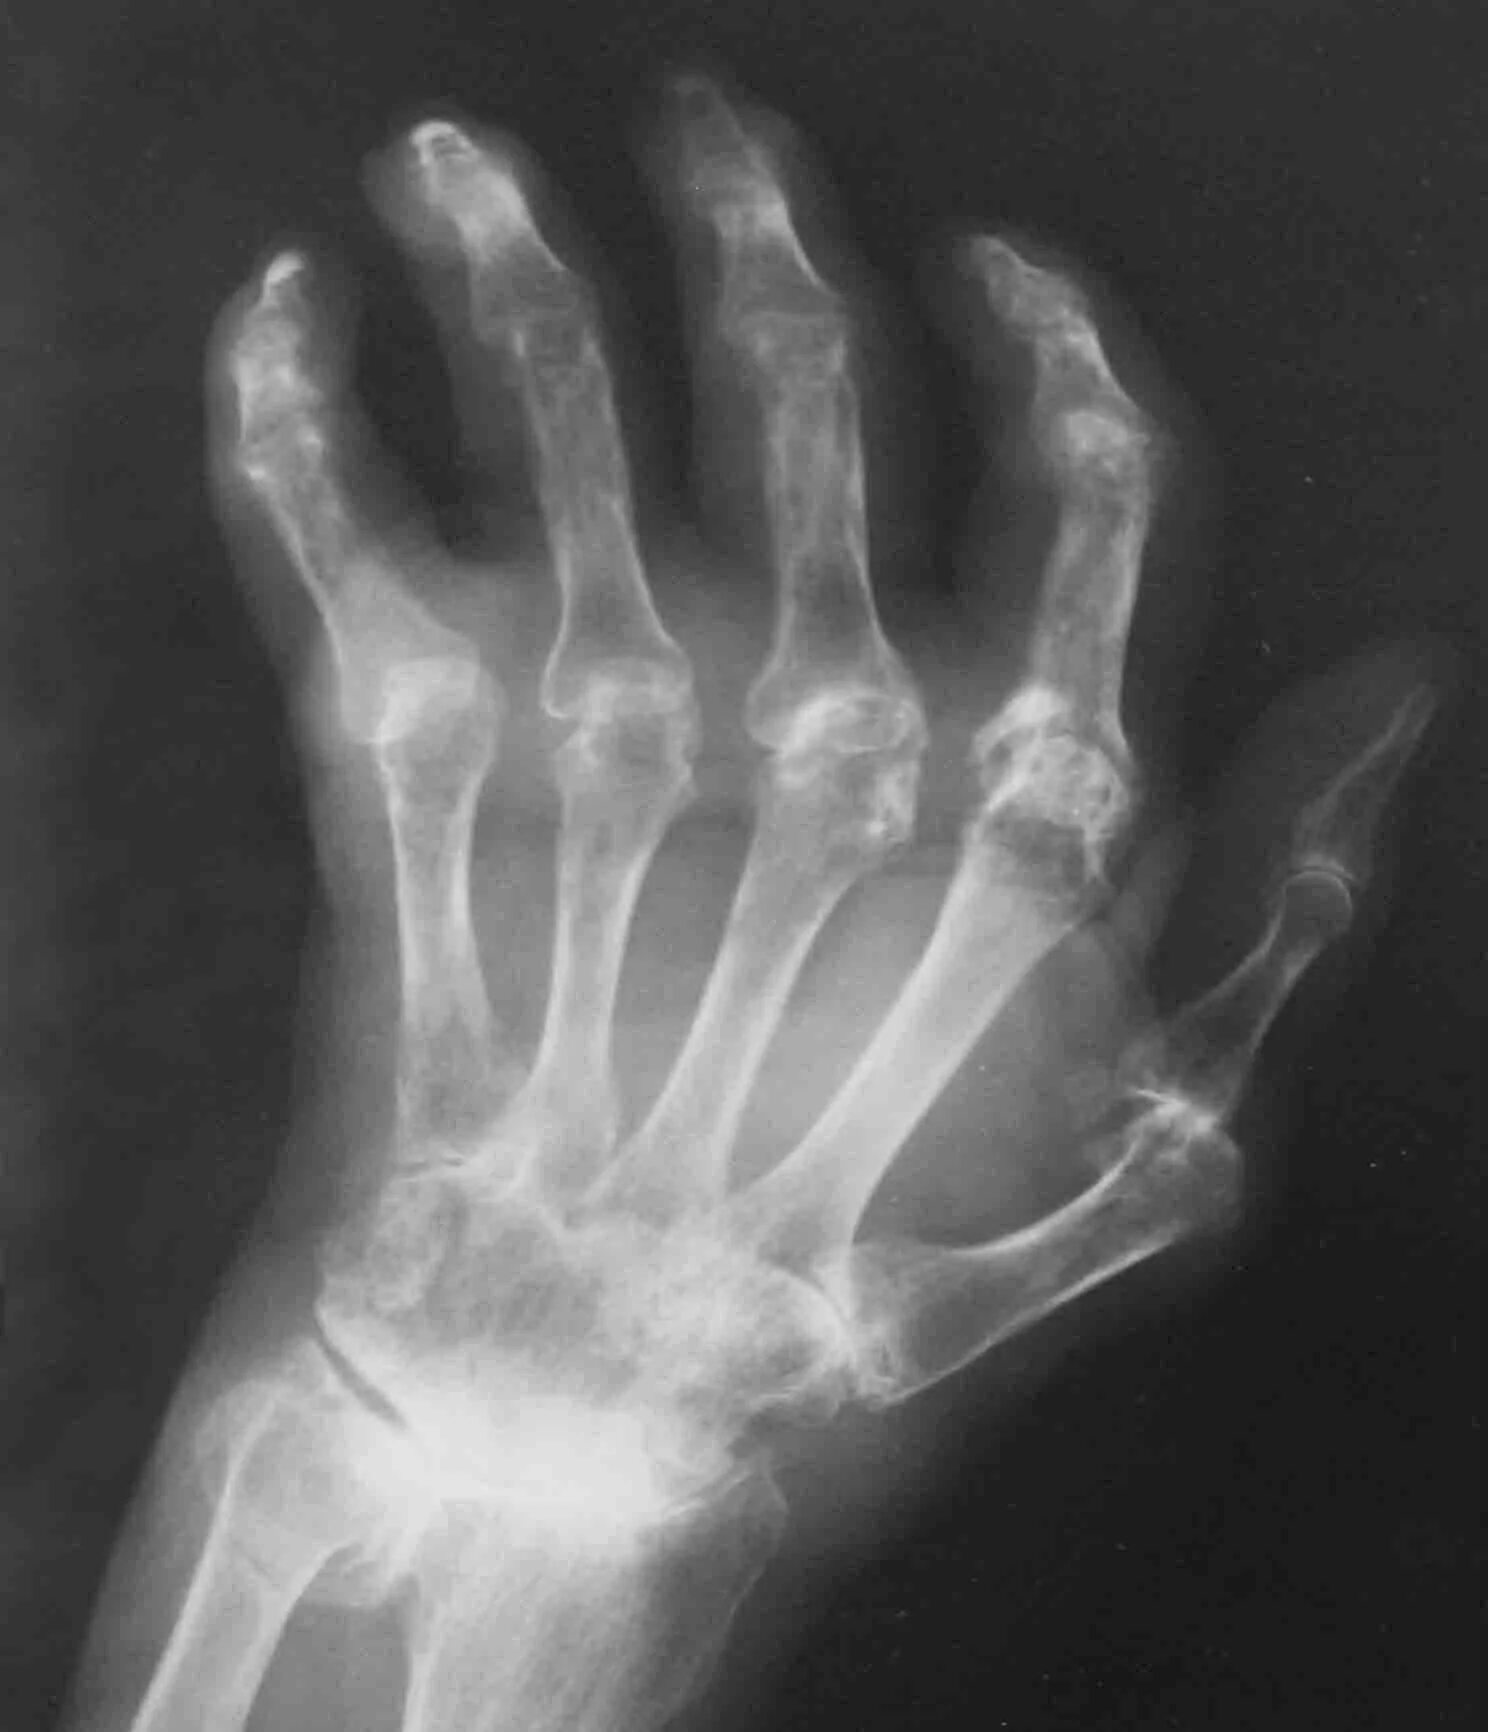

Поражение пястно фаланговых и проксимальных межфаланговых суставов